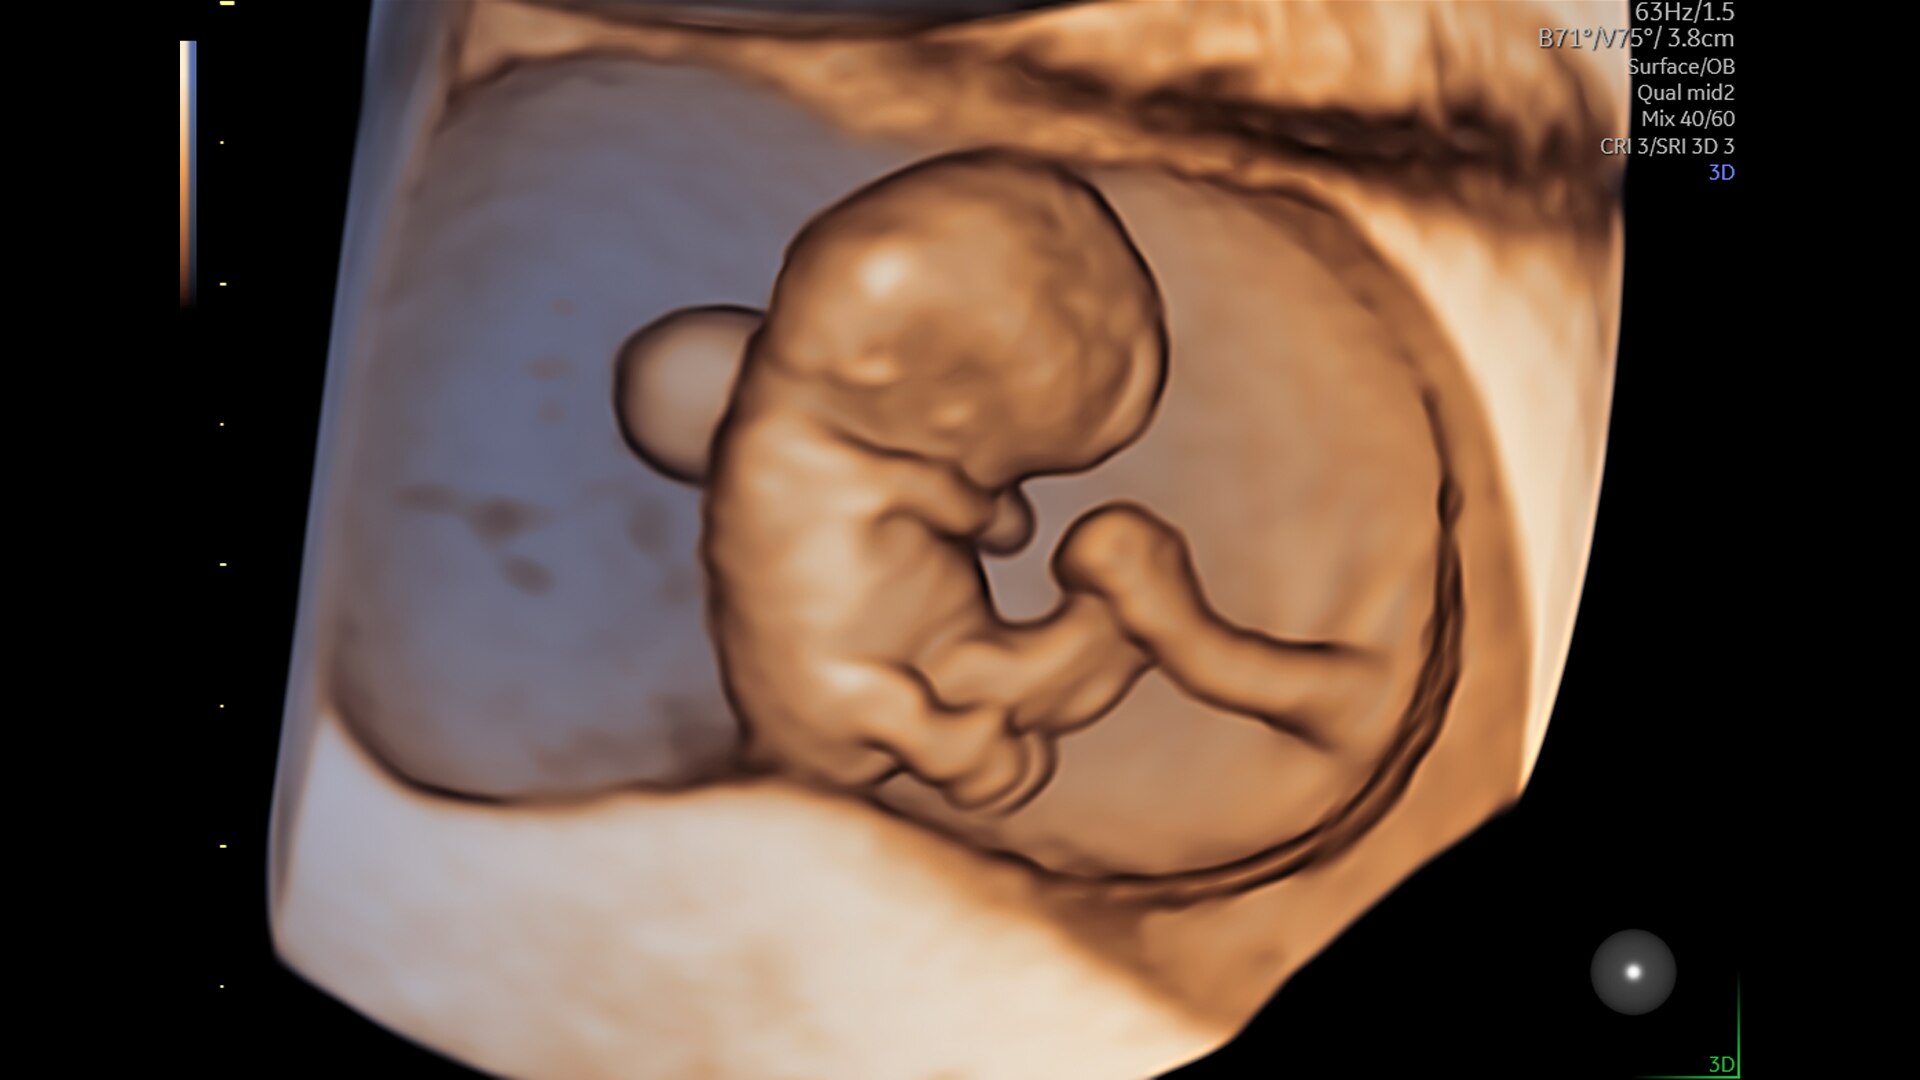

SonoLyst

SonoLyst* reduces the time to complete the standard ISUOG 2nd trimester exam requirements by 40%. And with SonoLyst live, it means no more stopping to freeze, annotate, or store.